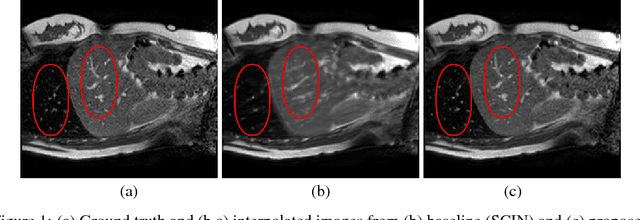

Abstract:Navigated 2D multi-slice dynamic Magnetic Resonance (MR) imaging enables high contrast 4D MR imaging during free breathing and provides in-vivo observations for treatment planning and guidance. Navigator slices are vital for retrospective stacking of 2D data slices in this method. However, they also prolong the acquisition sessions. Temporal interpolation of navigator slices an be used to reduce the number of navigator acquisitions without degrading specificity in stacking. In this work, we propose a convolutional neural network (CNN) based method for temporal interpolation via motion field prediction. The proposed formulation incorporates the prior knowledge that a motion field underlies changes in the image intensities over time. Previous approaches that interpolate directly in the intensity space are prone to produce blurry images or even remove structures in the images. Our method avoids such problems and faithfully preserves the information in the image. Further, an important advantage of our formulation is that it provides an unsupervised estimation of bi-directional motion fields. We show that these motion fields can be used to halve the number of registrations required during 4D reconstruction, thus substantially reducing the reconstruction time.